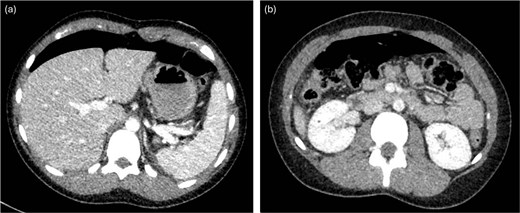

The gastroenterology team performed concurrent endoscopy using. With air insufflation and transillumination, a small pinpoint perforation was clearly identified on the anterior surface of the gastric-antrum (Figs 2 and 3).

Endoscopic view of the perforation. The picture in (a) demonstrates the site of the perforation. The picture in (b) shows the use of the overstitch technique to perform the closure endoscopically. Pictures (c) and (d) demonstrate the area of perforation once the first and second layers of endoscopic closure are completed, respectively.

To aid endoscopic visualization of the small perforation, a Maryland grasper was gently inserted into it (Fig. 2); the grasper’s tip, visualized endoscopically, confirmed the exact location. The remainder of the esophagus, stomach, and duodenum appeared normal. The Overstitch™ endoscopic-suturing device, mounted on a double-channel therapeutic endoscope and utilizing a tissue-helix for full-thickness bites, was used. Three full-thickness inverted figure-of-eight 2–0 Prolene sutures were placed at the perforation. Laparoscopic visualization confirmed full-thickness suture placement before the sutures were cinched, effectively closing the gastric wall defect (Fig. 3).